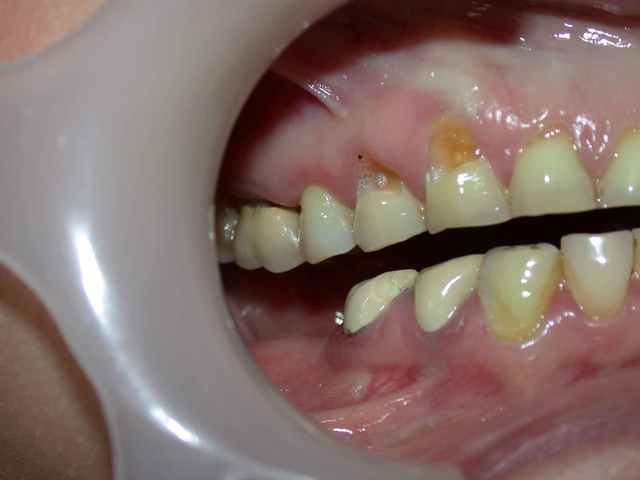

photos et pano du cas initial .

murielle a posté sur un cas de bruxisme en demandant quelle solution envisagée

alors je me lance et propose un cas similaire réalisé en plusieurs étapes ...